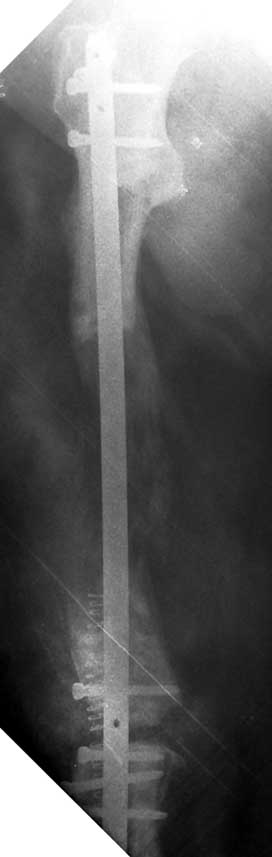

The duration of external fixation (external fixation index) depends on the amount of distraction required, and the extremity is prone to complications during this period. After the distraction phase is completed, the external fixator remains in place during the consolidation phase, which lasts twice as long as the distraction phase; but this period is hardly tolerated. If the external fixator is removed before sufficient consolidation is achieved, fractures, deformity and shortness will be the result. In our department, ‘lenghthening over nail’ method is used in order to decrease the external fixation index and increase patient comfort and activity level. In this method, the intramedullary nail is statically locked after the completion of the distraction phase, and external fixator is removed. The extremity is stabilized by the intramedullary nail during consolidation phase. In this way, complications due to long external fixation index or early removal of the external fixator are avoided.